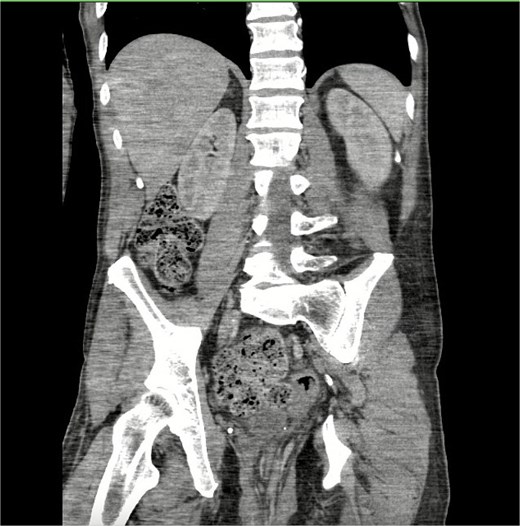

On arrival his haemoglobin was 10.2 g/dl (reference range 12.8–16.3 g/dl) and white blood cell count was 8.1 B/L (reference range 3.7–10.5 B/L) with neutrophilia (79.9%, reference range 40%–73%). On exam, the prolapse appeared to be full thickness with external hemorrhoids (Fig. 1). It was unable to be reduced at bedside therefore sugar was placed on the mucosa. A CT of the abdomen and pelvis with IV contrast was ordered and demonstrated a large rectal prolapse with extensive haemorrhoids and perirectal edema (Fig. 2). No definite rectal mass was noted. There was mild wall thickening of the sigmoid colon and constipation changes in the ascending and transverse colon. The following day the prolapse was temporarily reduced and the patient underwent a colonoscopy, demonstrating anterior rectal mucosal edema, fibrosis, and a possible mass. There was a rectosigmoid stricture 25 cm from the anal verge revealing friable edematous mucosa in the anterior rectal quadrant. Biopsies were taken and the decision was made to proceed with a proctectomy with end-colostomy. This procedure was performed prior to the return of biopsy results due to patient preference and our high index of suspicion for neoplasia.

CT scan of the rectal prolapse. CT of abdomen and pelvis revealed a large rectal prolapse with extensive hemorrhoids and perirectal edema.